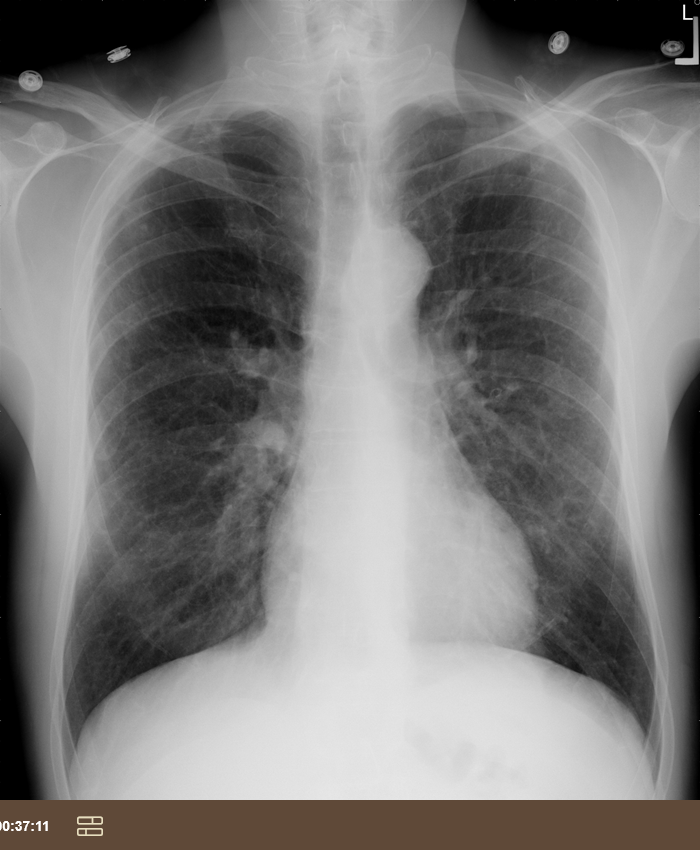

38F dry cough & malaise for 2 months

sarcoidosis (bilateral hilar adenopathy)

noncaseating granulamatous inflammation